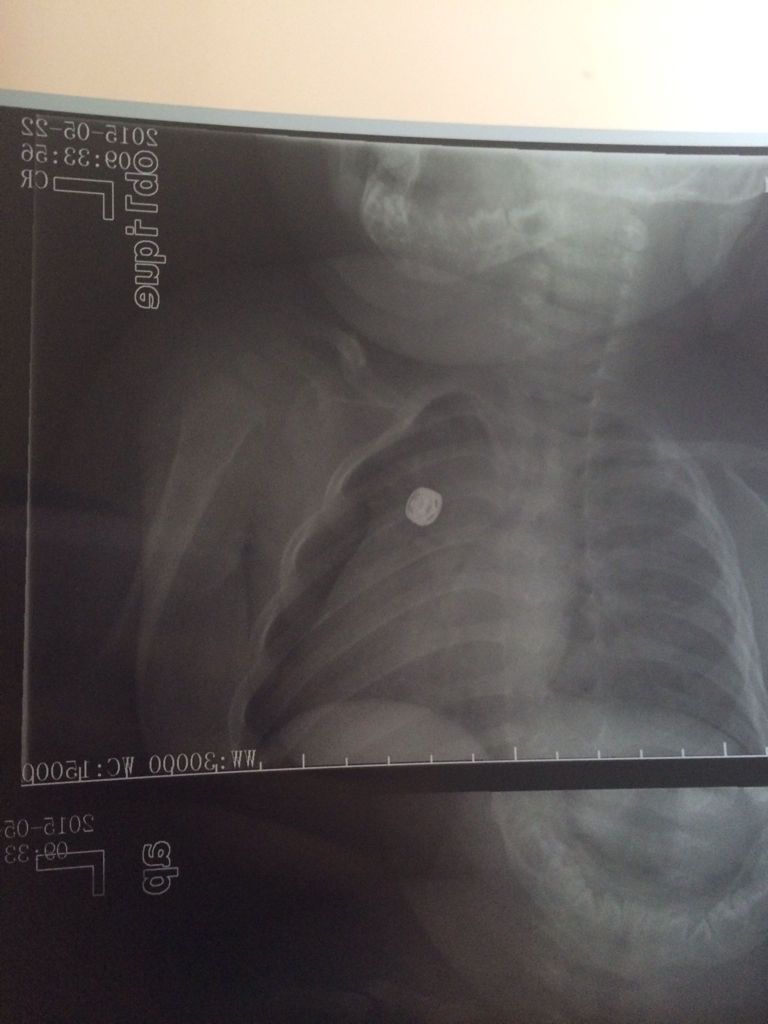

6个月宝宝左锁骨骨折,缠了八字绷带第二天左脸肿了怎么办 点击展开 匿名用户 2015-05-23 11:41 为您推荐: 其他回答 脸肿是因为绑得太紧,头面部的静脉回流不好导致的,建议到医院调整绑带的松紧度 笑天下美女 2015-05-23 12:43 相关问题 6个月宝宝从床上摔地上了,左侧朝下,左锁骨骨折了,医生缠了绷带,第二天左脸上 新生儿锁骨骨折错位了,当时拍片是发现,后来医生接了,还打了绷带,现在已经两周了,到医院复查后发现断 你好,我家宝宝17个月大了,锁骨骨折给她绑了8字绷带,绑了